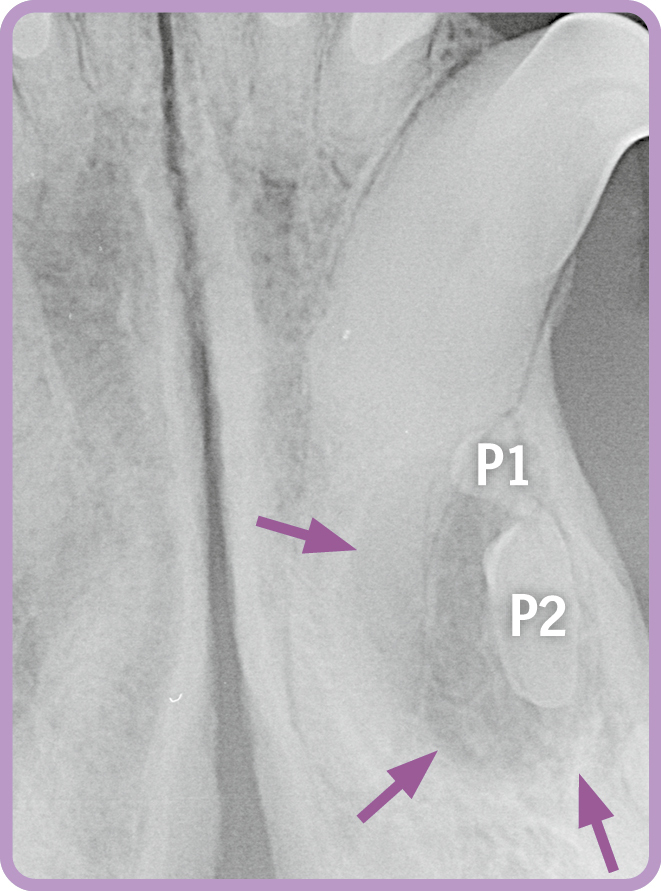

Der Röntgenbefund zeigt eine Retentionszyste (lila Pfeile) im Unterkiefer mit bereits erheblichem Ausmaß aufgrund des retinierten P1. Darüber hinaus ist bereits ein zweiter Prämolar in die Zyste involviert. Aufgrund dieses Befundes ist ein chirurgischer Eingriff zur Entfernung notwendig (Abb. 1).